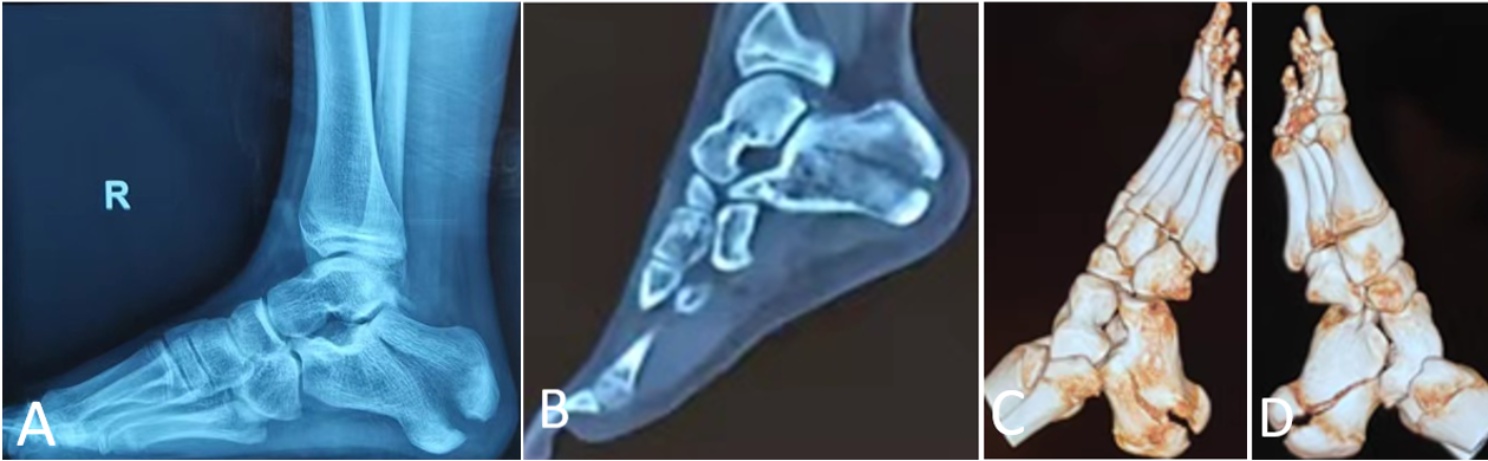

专科查体:右足跟部明显肿胀,局部可见皮肤淤青,足跟增宽,局部压痛明显,局部软组织肿胀,张力增高,后足轻度内翻畸形,足背伸活动受限,活动时足跟部疼痛加剧,双侧足背动脉波动均可触及,末梢感觉及血运良好。辅助检查:X线片显示右侧跟骨骨折伴关节面移位(图1(A)),CT平扫及三维成像提示右侧跟骨骨折断端移位明显,骨折线累及关节面,周围软组织肿胀(图1(B)~(D))。

(A):患者术前跟骨侧位X线片;(B)~(D):CT扫描显示跟骨多发透亮骨折线,伴骨折块明显移位、关节面受累及周围软组织肿胀,三维重建显示跟骨骨皮质多处连续性中断。

Figure 1. Preoperative imaging examination of the patient

1. 患者术前影像学检查